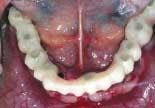

On the day of surgery, the remaining lower teeth are extracted (figure 3) and alveoplasty performed. Branemark Mk III TiU implants were placed in the 37, 36, 34, 44, 46, 47, and 31 sites. Branemark RS TiU implants were placed in the 43 and 33 sites. All implants were torqued to 45 Ncm. Multi-unit abutments were placed on the implants and torqued to 35 Ncm (figure 4). Bioss 1:1 autogenous grafting was done in the anterior region (figure 5) and the sites closed with chromic gut sutures. The maxillary CUD was inserted and the CLD was modified and relined with tissue conditioner.

The duplicate denture is relieved on the interior to allow it to be placed on the cast without interference and still articulate with the upper cast. The denture is luted to the upper cast with hot glue (figure 10). The denture is indexed to the lower cast utilizing a stiff polyvinyl bite registration material (figure 11). The denture is modified to allow clearance for the cylinders and returned to the cast using the index (figure 12). Temporary cylinders are placed on the lower cast (figure 13). Cold-cure Jet Acrylic is injected around the cylinders and denture to fill the spaces (figure 14). The denture is wrapped with elastics and placed in a pressure pot to cure. Following curing, the denture is removed from the cast by unscrewing the cylinders (figure 15). The denture is now formed to become a fixed provisional by grinding away the excess acrylic (figure 16).